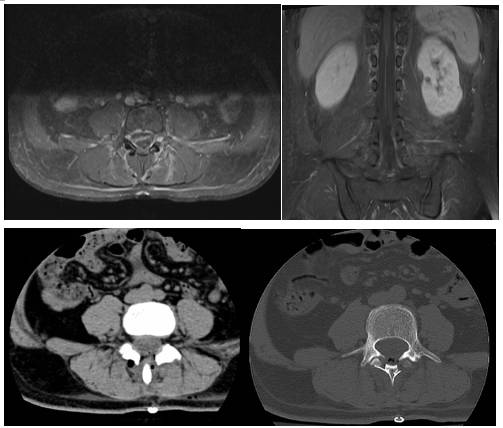

术前科室讨论,根据CT及MRI检查,诊断患者腰4椎管内占位明确,伴有明显钙化,性质考虑为神经鞘瘤或畸胎瘤等可能(图1)。有明确手术指征,患者及其家属商量后决定手术治疗。

图1. 术前CT及MR